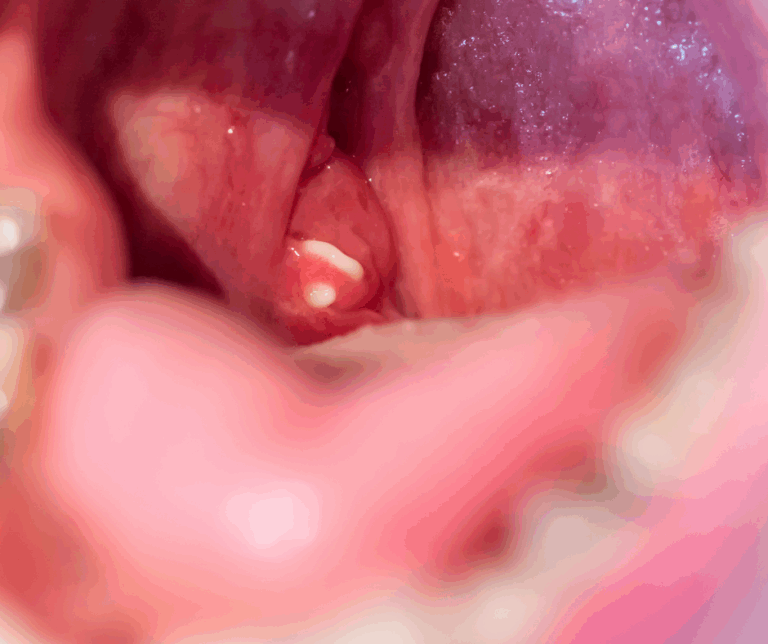

Tanda lain termasuk sakit tekak berulang, kesukaran menelan, rasa sesuatu tersangkut di kerongkong serta bintik putih pada tonsil. Kadangkala batu ini terkeluar sendiri ketika batuk atau makan, tetapi mudah terbentuk semula jika tidak dirawat.

Permukaan tonsil dilapisi mukus dan mempunyai lubang kecil atau kripta, yang jumlahnya berbeza bagi setiap orang. Di sinilah sisa makanan, bakteria dan kotoran boleh tersangkut lalu mengeras menjadi batu tonsil. Jika tonsil kerap meradang atau mudah teriritasi, risiko terbentuknya batu tonsil akan lebih tinggi.